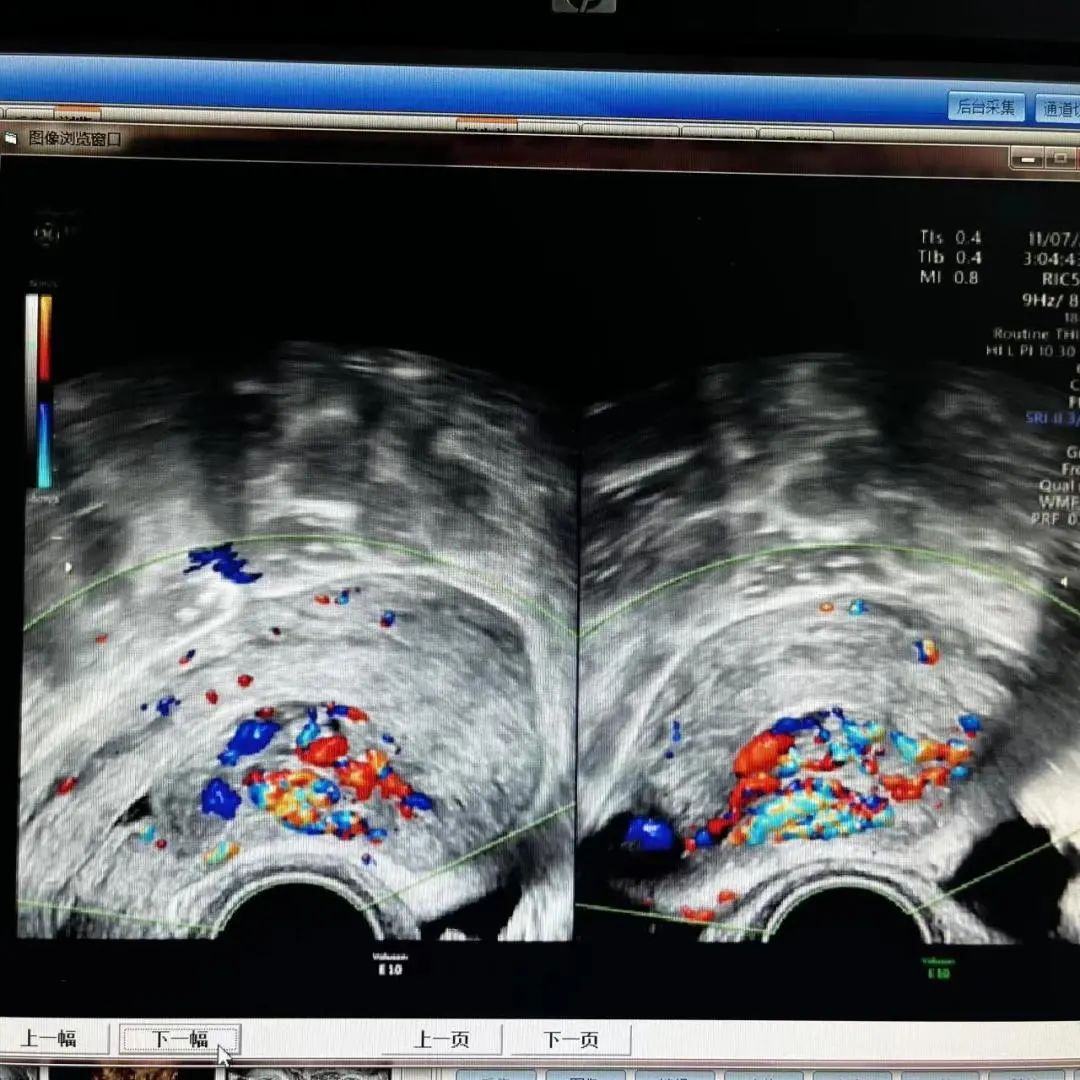

编者按 剖宫产瘢痕妊娠,是指受精卵在子宫切口上着床,在临床上这种情况要引起高度的重视,会随着妊娠囊的增大,造成局部的破裂,后果非常严重。本期【病例分析室】由山西省人民医院主任医师王素琴为大家分享一例剖宫产瘢痕部位妊娠(药流后)合并动静脉瘘,对于此情形,她是如何进行诊断和治疗的,详见以下病例分析。 病例介绍 患者29岁,主因“药流后2月,发现瘢痕妊娠4天”入院。 现病史:停经40天于当地医院行药流术,术后20天盆腔彩超未见异常。术后2月因“月经未复潮”就诊于我院,行盆腔彩超提示:瘢痕妊娠III型,动静脉瘘不除外。考虑“瘢痕妊娠”入住我科。血HCG:229.56mIu/mL。追问病史:药流术后未同房。 既往史:2009年、2021年于当地医院行剖宫产术。 婚育史:G4P2。 月经史:平素月经规律,5/25天,LMP:2022-07-01。 妇科检查:外阴正常,已婚未产型;阴道通畅,可见少许分泌物;宫颈光滑,前穹隆呈紫蓝色,触血阴性;宫体前位,大小约7*6cm大小,表面光滑,活动好,无压痛;双附件区未见明显异常。 辅助检查: 1)盆腔彩超: 子宫前壁下段瘢痕处可见44.4*34.3mm混合回声包块,向膀胱隆起,包块与膀胱间肌层变薄,厚约0.7mm,CDFI:包块内部及周边可见极丰富血流信号,可探及动静脉血流谱。考虑子宫前壁下段瘢痕处混合回声包块(瘢痕妊娠III型,动静脉瘘不除外)。 2)盆腔核磁: 子宫前壁下段瘢痕处及宫腔内见团块状异常信号影;病变周缘伴粗大迂曲血管。 3)血HCG:229.56mIu/mL。 术前诊断:剖宫产部位瘢痕妊娠III型(药流后)动静脉瘘?